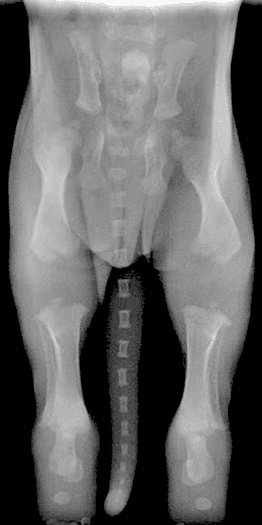

- La radio des hanches n’est pas non plus exempt d’erreurs…

- Mauvaise position du chien à la radiographie

- Mauvaise interprétation à la lecture de la radio des hanches

- La dysplasie des hanches évoluant avec le temps, il est totalement inefficace de radiographier les hanches d’un chien trop jeune… Idéalement, les radios des hanches ne devraient pas être envisagées avant l’âge de trois ans.